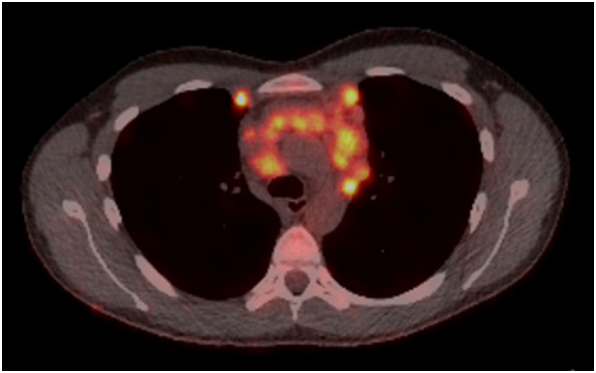

Step 2

A PET CT scan was subsequently performed. It demonstrated marked metabolic activity, indicating an aggressive process.